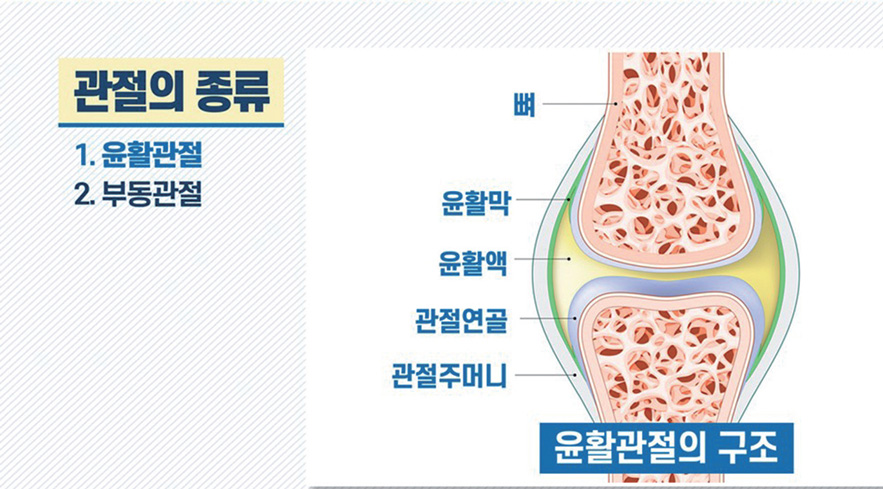

자동차 엔진에 엔진오일이 없다면 빡빡해져서 피스톤 운동이 제대로 안 되겠죠. 마찬가지로 항상 움직여야 하는 가동성 관절면은 섬유피막으로 쌓여 있고 이 내부의 막에서 매끄러운 윤활액을 분비해 부드럽게 움직일 수 있어서 이 모든 가동관절을 윤활관절潤滑關節(Synovial joint)이라고도 부릅니다.

가동관절(윤활관절)의 구조